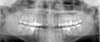

Toutes les dents sont donc visibles sur le même cliché ainsi que :

- Les arcades dentaires

- Les maxillaires supérieurs et inférieurs

- La partie basse des fosses nasales

- Le plancher des sinus maxillaires

En plus de l'étude des soins déjà effectués, ou à effectuer, sur les dents (traitement de caries, couronnes…), la panoramique dentaire permet de dépister les problèmes éventuels des dents, des maxillaires et des sinus, en particulier :

- Les caries

- La position des dents de sagesse dans les maxillaires

- L'existence de kystes dentaires à l'extrémité des racines

- Les dents surnuméraires

- Les agénésies dentaires (absence des germes des dents)

- L'évaluation générale de la perte de l'os de soutien des dents (parodontite)

- Les tumeurs

L’examen permet également de localiser l'emplacement des cavités naturelles (avant d'envisager la pose d'un implant dentaire par exemple) et le trajet du nerf mandibulaire.

- Chez l'enfant, la panoramique dentaire permet de visualiser les germes des dents définitives, c'est-à-dire des futures dents de l'adulte. Ceci autorise l'évaluation de l'âge dentaire.